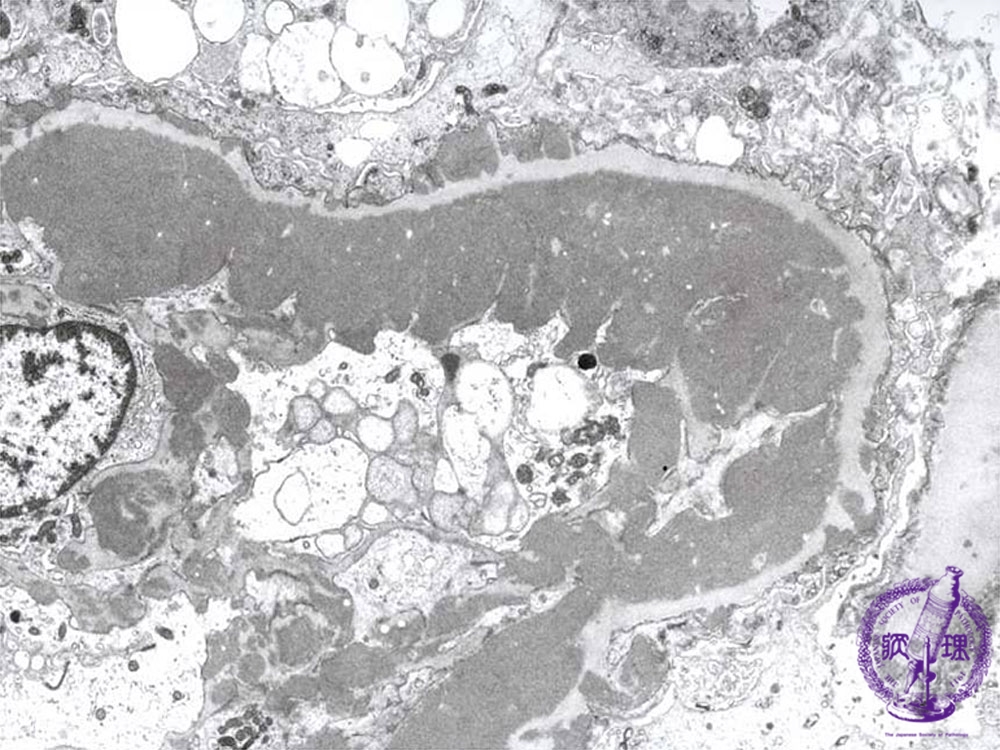

- (6)Lupus Glomerulonephritis

Microscopic findings (electron microscopy): There are electron dense subendothelial deposits (yellow dotted line) which correspond to the wire-loop lesion.